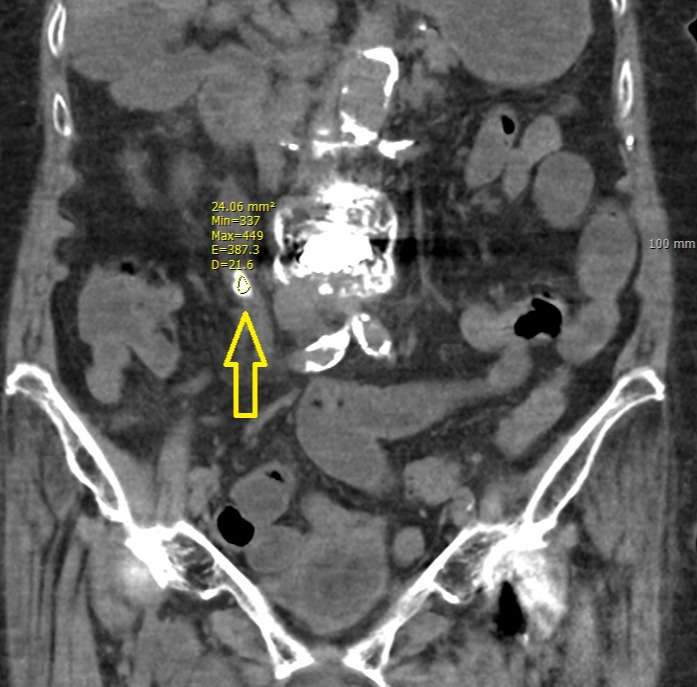

요산결석은 방사선 투과성(radiolucent)이 높아서, 전통적인 X-ray 검사에서는 주변 조직과의 밀도 차이가 크지 않아 잘 보이지 않는다. 칼슘결석에 비해 밀도가 낮아 X-ray를 투과시키므로, 단순 X-ray 영상에서 뚜렷하게 구별되지 않는다. 그래서 ESWL 시행 시 요산석은 잘 보이지 않는 경우가 많아서 쇄석 진행 시 조영제를 사용해야 할 수 있다. 결론적으로 복부 CT를 찍어서 결석 병변을 확인하는 것이 가장 정확하다. (CT 역시 방사선을 이용하지만 CT는 밀도 차이에 민감하게 반응하므로, 요산결석이 주변 조직보다 밀도가 높은 경우 상대적으로 하얗게 표시되고 이를 통해서 결석의 유무를 감별하게 된다.) 특히나 돌의 유무만 본다고 하면 조영제의 사용없이 저선량 복부 CT를 촬영해 볼 수 있으며 요산 결석의 체외 충격파 쇄석술 이후 돌의 위치나 파쇄 정도와 같은 변화를 관찰하기 위해서 필히 진행되는 검사 중 하나이다.

기본적으로 일반 엑스선 촬영(K.U.B 사진, Kidney, Ureter, Bladder)으로는 보이지 않지만 CT 에는 보이고 그 크기가 4mm가 넘으면서 소변의 산도(pH)가 5.5 미만이면 요산석의 가능성은 거의 90% 이상된다.

CT는 Hounsfield Unit(HU)이란 지표를 활용하여 조직의 밀도를 정량화할 수 있다. 대부분 요산결석의 경우, 일반적으로 200~500 HU 범위로, 칼슘결석(800~1,000 HU)보다는 낮지만 주변 연부조직(근육: 40~60 HU, 지방: -100~-50 HU)보다는 밀도가 높다. 대개의 경우 이 HU 값이 높을수록 그 돌은 단단한 돌이다.

요산석 HU.jpg 화살표로 가리키는 물체가 요관 내 위치한 요산석. 관심 영역 내에 HU 337~449를 보이고 있다.